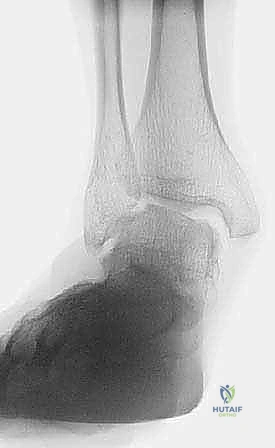

* الأشعة السينية أثناء الوقوف (Weight-bearing X-rays): ضرورية جداً لتقييم الانهيار العظمي، زوايا المفاصل، ومدى ميلان العظم الكاحلي.